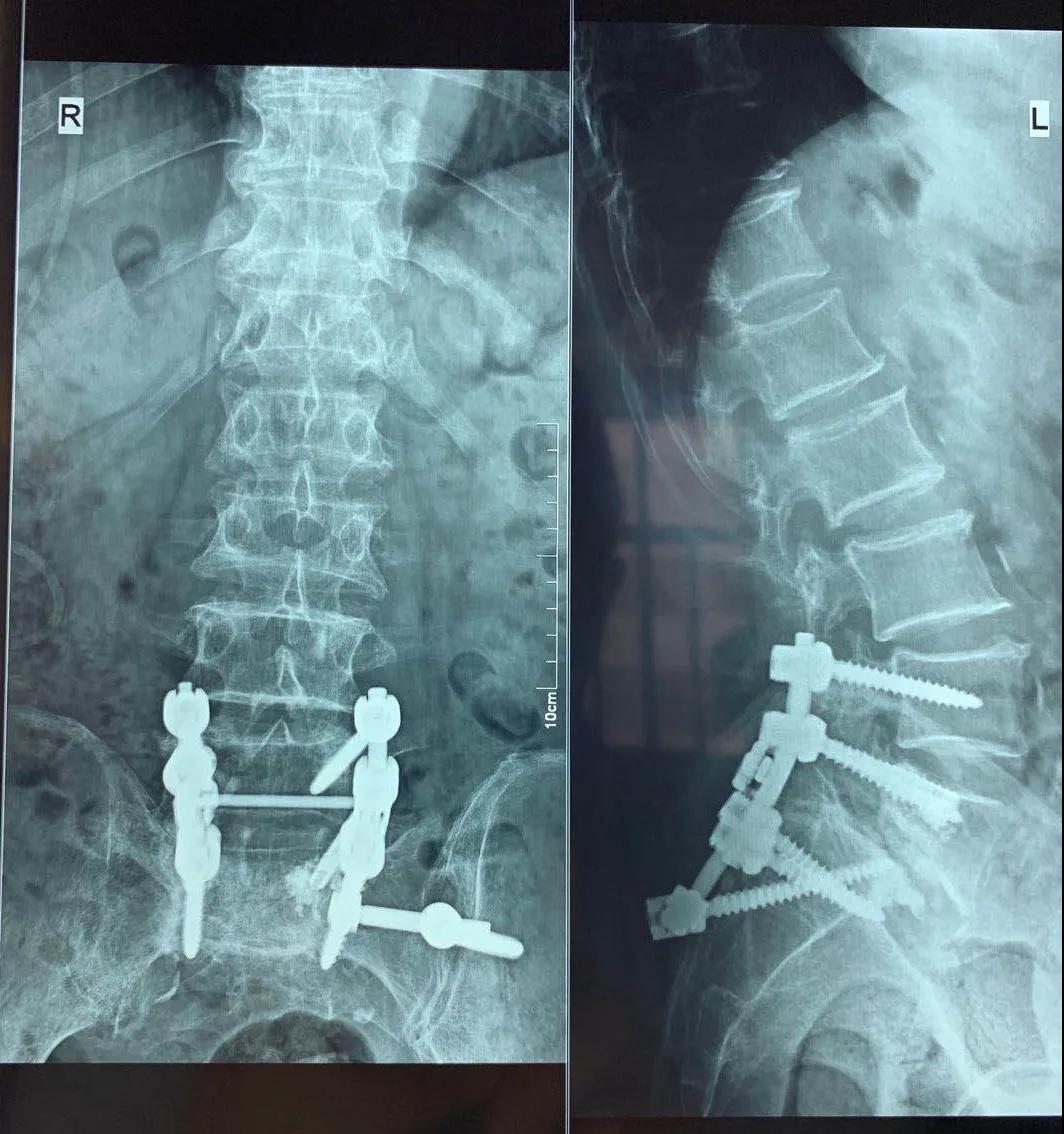

手術前

手術后

科室綜合分析患者現(xiàn)在的病情,考慮手術內(nèi)固定失效是引起癥狀的主要原因,決定給予行腰椎滑脫內(nèi)固定翻修術,在院領導、麻醉科和手術室的支持下,充分論證手術可能存在的風險及相關處理方案,向患者及家屬詳細的介紹病情及治療方案,取得患者及家屬的同意,完善術前準備,骨二科許冬雷專家團隊于6月23日全麻下行腰椎滑脫內(nèi)固定失效翻修術,術中給予去除移位的椎間融合器,更換腰5左側的椎弓根螺釘,考慮患者為骨質(zhì)疏松患者,更換的椎弓根釘為骨水泥型椎弓根釘,并考慮患者單純骶1螺釘固定應力較大,給予增加左側髂骨釘固定,術中透視確認內(nèi)固定位置,手術順利,患者入ICU監(jiān)護治療,術后第一天患者自述腰痛及下肢疼痛消失,雙下肢自主活動及感覺正常,雙膝伸直受限明顯好轉,可伸直至80°,術后三天出ICU返回病房,給予復查X線平片及CT檢查,見滑脫椎體大部復位,并更換的椎弓根螺釘及髂骨釘位置良好,繼續(xù)給予理療及功能鍛煉,現(xiàn)能主動伸直至膝關節(jié)屈曲60°位,下一步擬患者腰部手術恢復后行頸椎微創(chuàng)射頻治療,緩解患者的髖膝周圍肌肉張力,進一步緩解患者的髖膝關節(jié)功能。